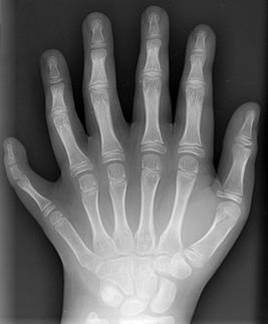

What is polydactyly?

A genetic disorder where babies are born with extra fingers or toes

What is this?

An x ray showing polydactyly